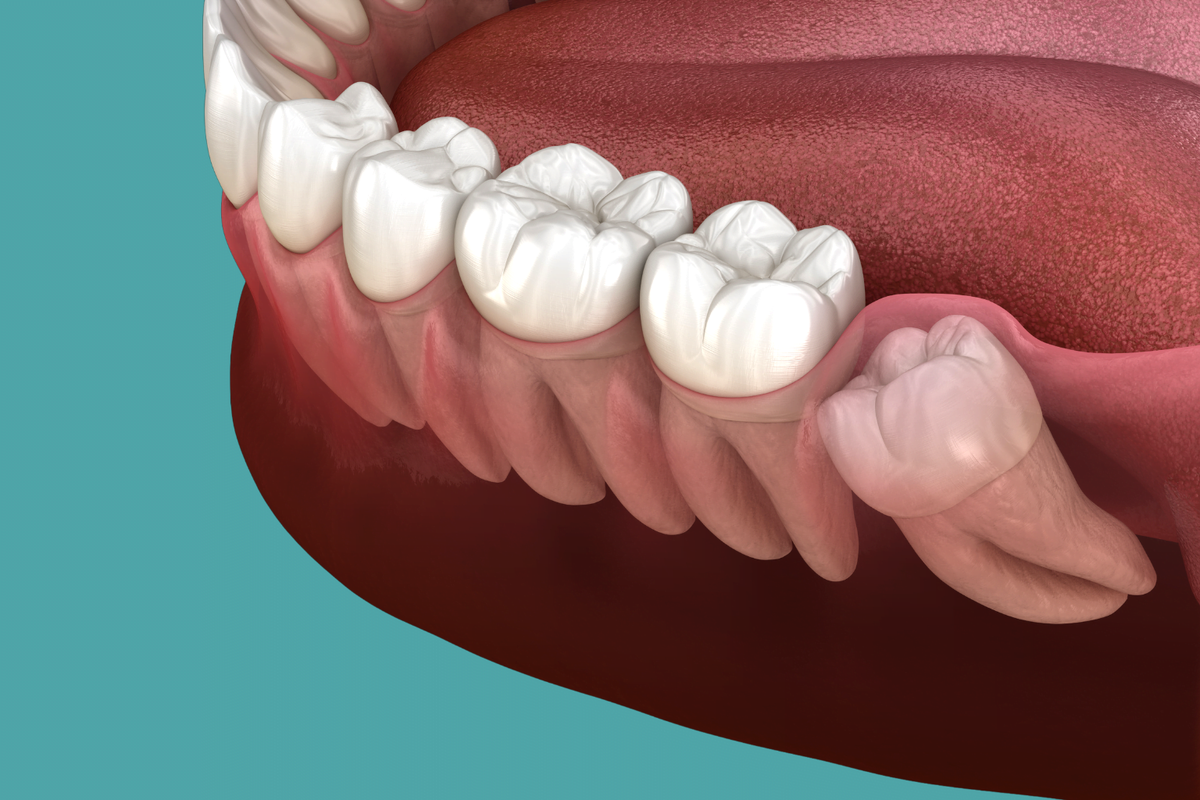

Основная проблема «восьмерок» заключается в сложном прорезывании. Лишь небольшой процент людей испытывает легкий дискомфорт. Челюстная кость во взрослом возрасте уже сформирована, поэтому места для них может и не быть. Это вызывает ряд проблем, которые могут потребовать оперативного вмешательства.

· Частичное прорезывание. Небольшая часть зуба появляется над десной, а дальнейший рост не происходит.

· Дистопия. «Восьмерка» может сильно выступать из зубного ряда. Это вызывает травму слизистой и приводит к появлению ранок и эрозии.